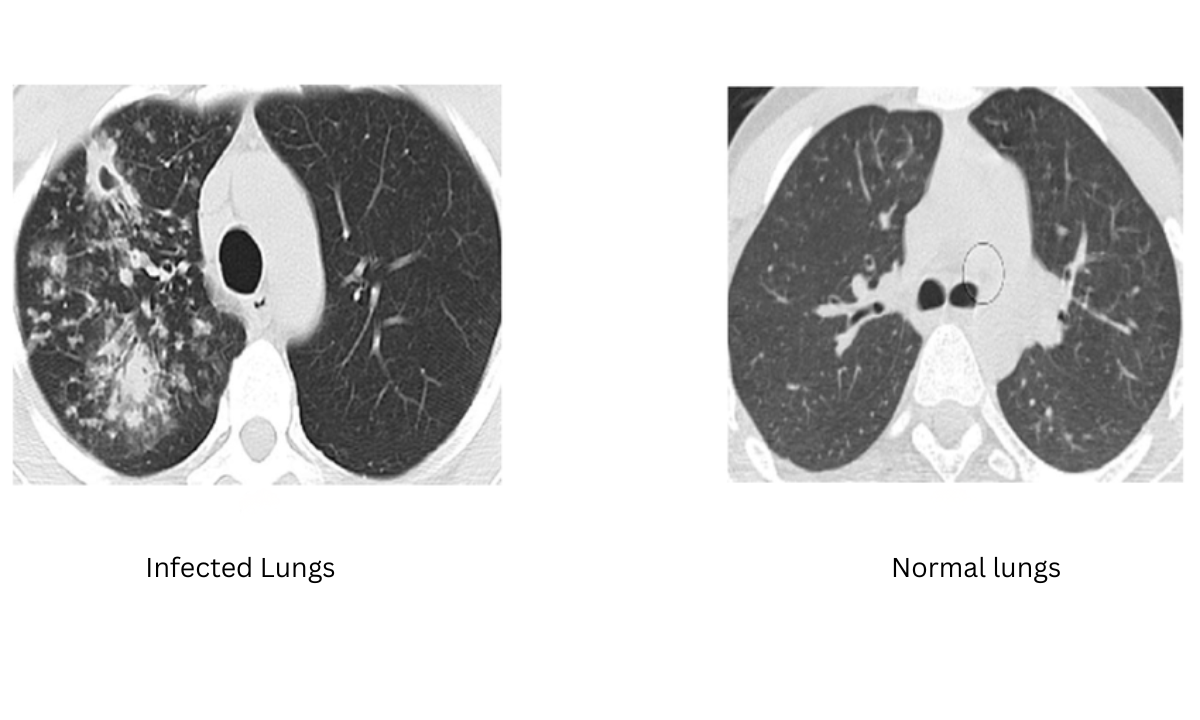

4. Imaging Tests

Imaging helps detect lung abnormalities.

- X ray in Bangalore facilities are widely available for quick screening.

- CT scan chest in Bangalore provides more detailed images.

A CT scan gives a clearer picture of lung damage and complications.

Role Of Imaging In TB Diagnosis

Imaging plays an important role in confirming TB, especially pulmonary tuberculosis.

| Imaging Method | When Used | Benefit |

|---|---|---|

| Chest X-ray | Initial evaluation | Quick and affordable |

| CT Scan | Detailed assessment | Detects early changes |

If an X-ray result is unclear, doctors may recommend a CT scan for better clarity.